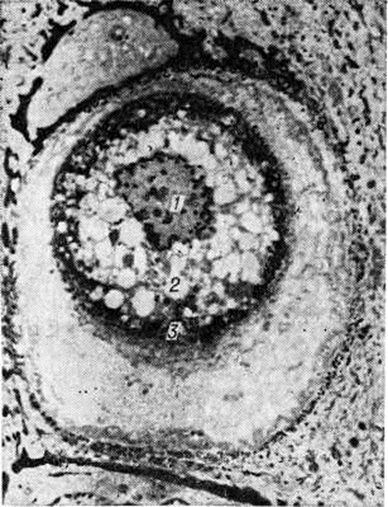

В основе Дискератоз лежит нарушение комплекса тонофибриллы — десмосомы, выражающееся в растворении контактного слоя десмосом с последующим отрывом от них тонофибрилл, которые скопляются вокруг ядра. В круглых телах тонофибриллы располагаются вокруг ядра в виде плотных, кератиноподобных пучков, окружающих деструктивно изменённую центральную часть цитоплазмы (рисунок 2). Дальнейшее уплотнение и уменьшение количества кератина в этих клетках с образованием пустых зон приводит к образованию зёрен.